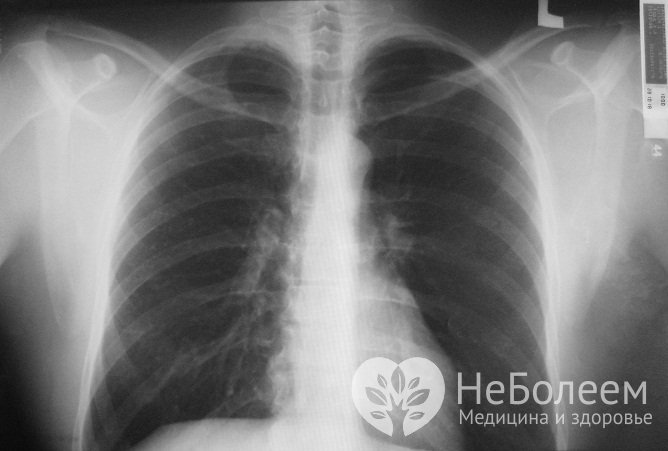

Для постановки диагноза бронхита у детей проводится комплексное обследования, в том числе – рентгенография легкихДифференциальная диагностика проводится с бронхиальной астмой, пневмонией, бронхоэктатической болезнью, туберкулезом.